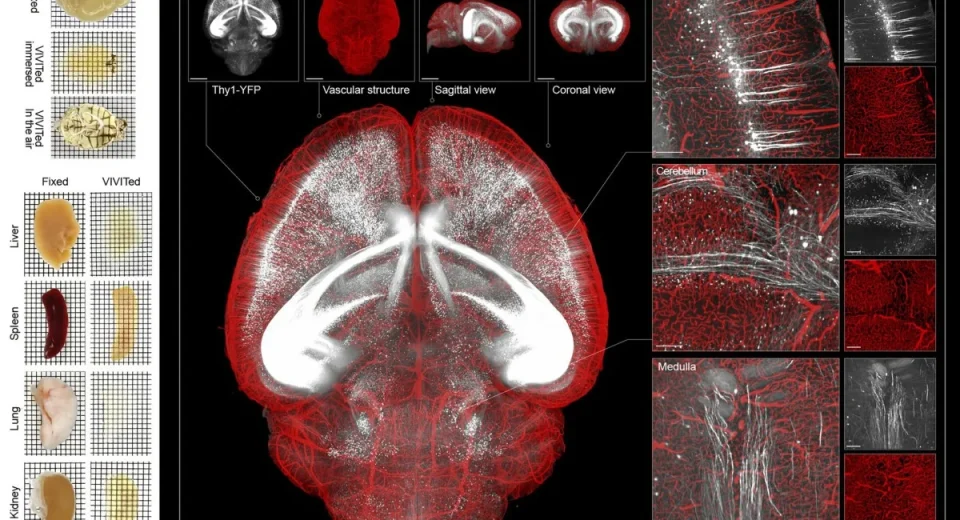

சீனாவில் அறுவை சிகிச்சை செய்யாமல், மூளையில் ஏற்படும் துல்லியமான மாற்றங்களைக் கண்டறிவதற்கு உதவும் அதிநவீன MRI இமேஜிங் ஸ்கேன் கண்டுபிடிக்கப்பட்டுள்ளது. சீனாவின் தியான்ஜின் பல்கலைக்கழக விஞ்ஞானிகள் இதனை உருவாக்கி சாதனை படைத்துள்ளனர். மூளை-கணினி இடைமுக (BCI) தொழில்நுட்பத்தில் பயன்படுத்தக்கூடிய வகையில் இந்த MRI ஸ்கேன் கண்டுபிடிக்கப்பட்டுள்ளது. இந்த அதிநவீன MRI இமேஜிங் ஸ்கேன் கடுமையான நரம்பு நிலைகளைக் கண்காணிக்கவும் மற்றும் மன ஆரோக்கியத்தை மதிப்பிடவும் உதவும் எனக் கூறப்படுகிறது. புதிய தொழில்நுட்பத்தின் மூலம் அல்சைமர், பார்கின்சன் மற்றும் […]